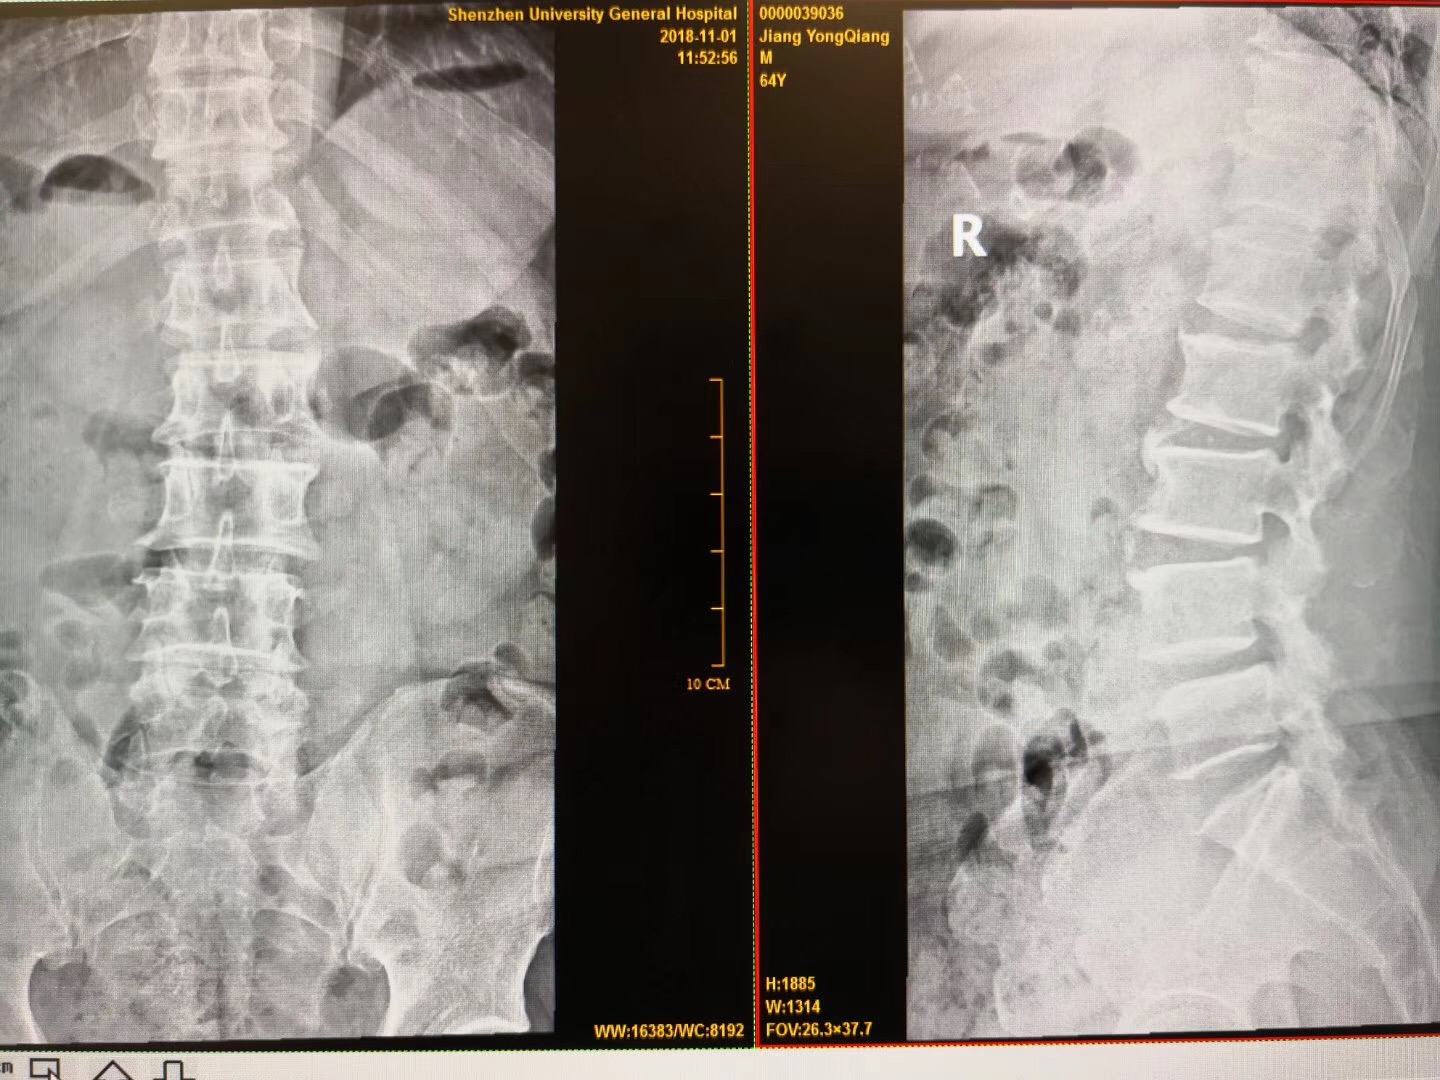

磁共振矢状位显示腰4椎体滑脱,腰4/5椎间盘突出,相应层面椎管狭窄